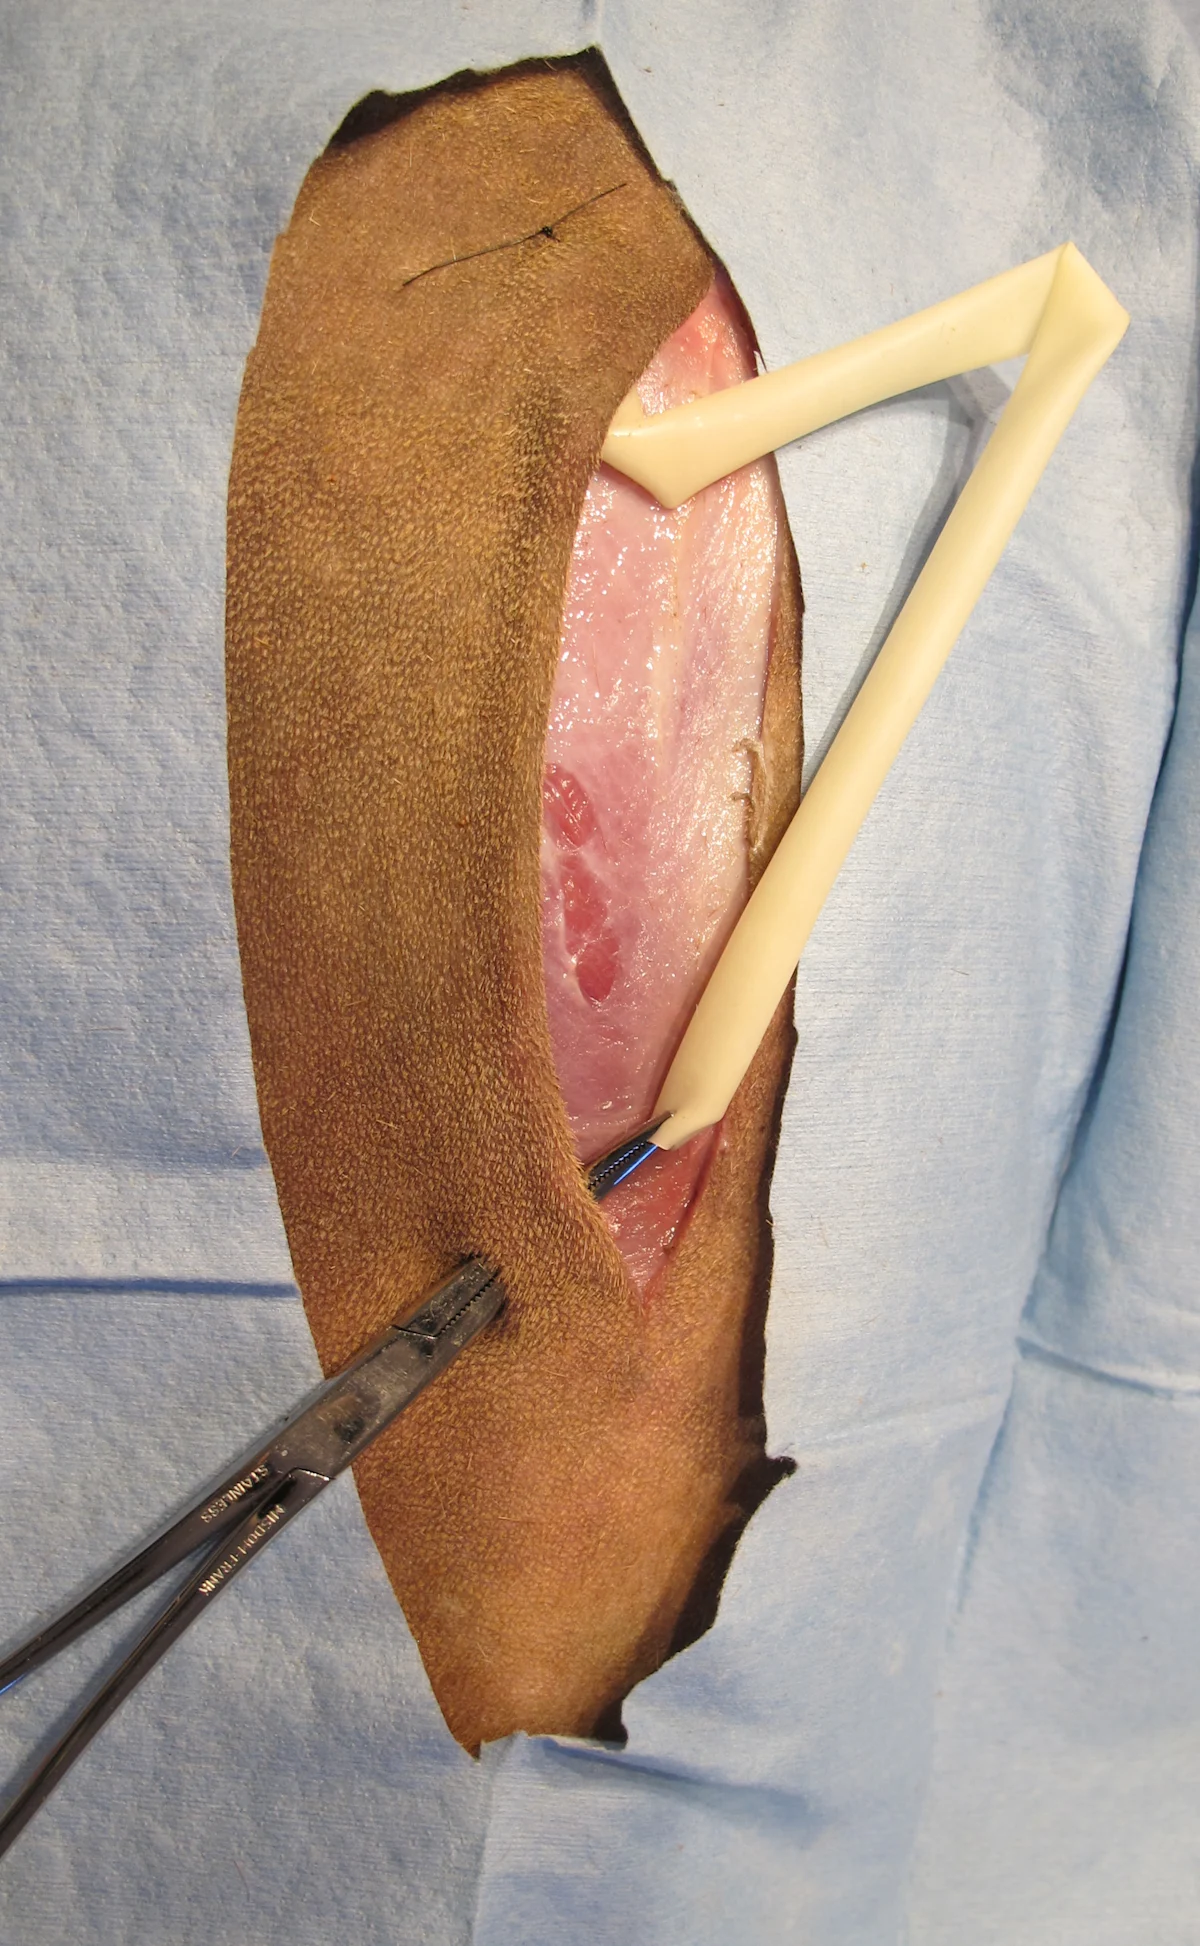

Step 3

Select the exit site. Exit passive drains from the most dependent area of the wound. Active drains can be exited wherever it is most convenient to secure the drainage reservoir. (A) Tent the skin with hemostats, then make a stab incision. (B) Spreading the tips and using them to tent the skin facilitates the incision process while protecting deeper tissues. Some active drainage systems come armed with a trocar that is used to exteriorize the drain through the skin.

A